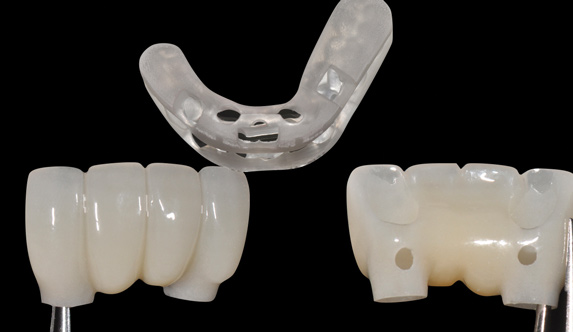

Fig 14. The printed static guide is used to precisely control preparation of osteotomy (Fig 14) and delivery of the implant through the guide (Fig 15).

Figure 14

Fig 15. The printed static guide is used to precisely control preparation of osteotomy (Fig 14) and delivery of the implant through the guide (Fig 15).

Figure 15

Fig 16. Presurgical design and fabrication of restorative components based on virtual implant position allow for possible minor angle/linear deviations (Fig 16 through Fig 18). Component options are broad and may include a custom healing abutment and bondable polymethyl methacrylate restoration; a single restoration with an engaging or non-engaging base; provisional fixed partial dentures (Fig 19), which can be indexed intraorally to prepared temporary abutments; or a full-arch restoration to be indexed intraorally to prepared temporary abutments.

Figure 16

Fig 17. Presurgical design and fabrication of restorative components based on virtual implant position allow for possible minor angle/linear deviations (Fig 16 through Fig 18). Component options are broad and may include a custom healing abutment and bondable polymethyl methacrylate restoration; a single restoration with an engaging or non-engaging base; provisional fixed partial dentures (Fig 19), which can be indexed intraorally to prepared temporary abutments; or a full-arch restoration to be indexed intraorally to prepared temporary abutments.

Figure 17

Fig 18. Presurgical design and fabrication of restorative components based on virtual implant position allow for possible minor angle/linear deviations (Fig 16 through Fig 18). Component options are broad and may include a custom healing abutment and bondable polymethyl methacrylate restoration; a single restoration with an engaging or non-engaging base; provisional fixed partial dentures (Fig 19), which can be indexed intraorally to prepared temporary abutments; or a full-arch restoration to be indexed intraorally to prepared temporary abutments.

Figure 18

Fig 19. Presurgical design and fabrication of restorative components based on virtual implant position allow for possible minor angle/linear deviations (Fig 16 through Fig 18). Component options are broad and may include a custom healing abutment and bondable polymethyl methacrylate restoration; a single restoration with an engaging or non-engaging base; provisional fixed partial dentures (Fig 19), which can be indexed intraorally to prepared temporary abutments; or a full-arch restoration to be indexed intraorally to prepared temporary abutments.

Figure 19